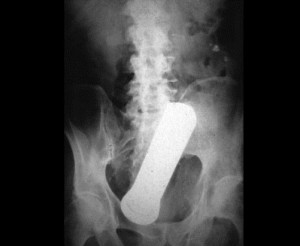

ნათურა

8 (1)